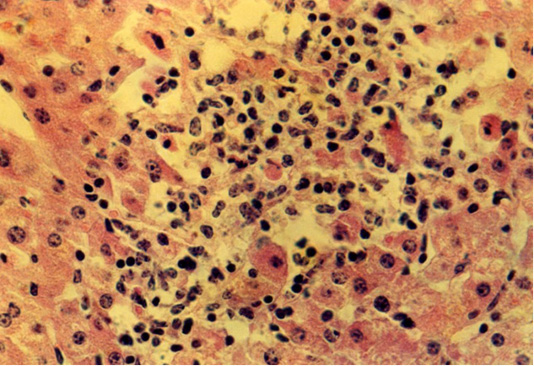

Isolated location of hepatocytes amid lymphocytes and macrophages at fasciolosis of the second group animals. Hematoxylin and eosin. Image scale 400:1.